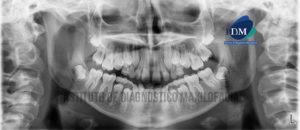

Paciente masculino de 64 años acude al Instituto de Diagnóstico Maxilofacial para la evaluación imagenológica de control. A la evaluación de la radiografía panorámica se